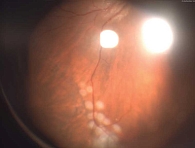

Рис. 1. Фото глазного дна левого глаза после первого этапа операции (тампонада силиконовым маслом; в верхненаружном квадранте визуализируется зона бывшего ретиношизиса, отграниченная лазеркоагулятами)

На первые сутки после операции МКОЗ левого глаза составила 0,2. Сетчатка прилежит во всех отделах, зона ретиношизиса и разрыв блокированы лазеркоагулятами. Офтальмогипертензия (ВГД OS – 28 мм рт. ст.) купирована с помощью инстилляций гипотензивных капель. Пациент выписан на вторые сутки под амбулаторное наблюдение с соответствующими рекомендациями (рис. 1 и 2).